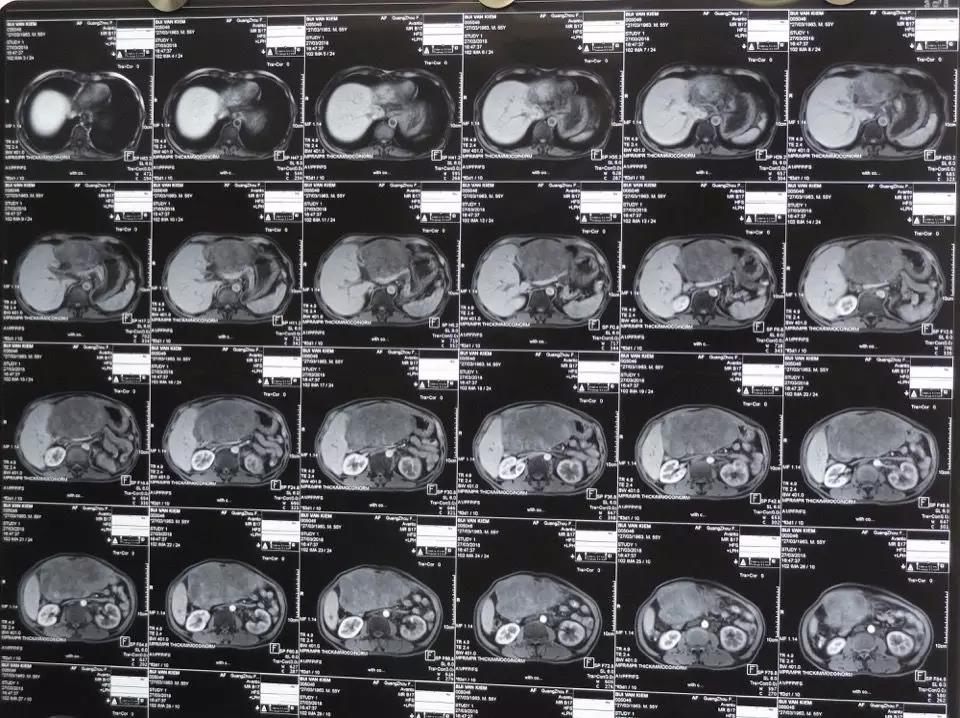

術(shù)前CT檢查圖。